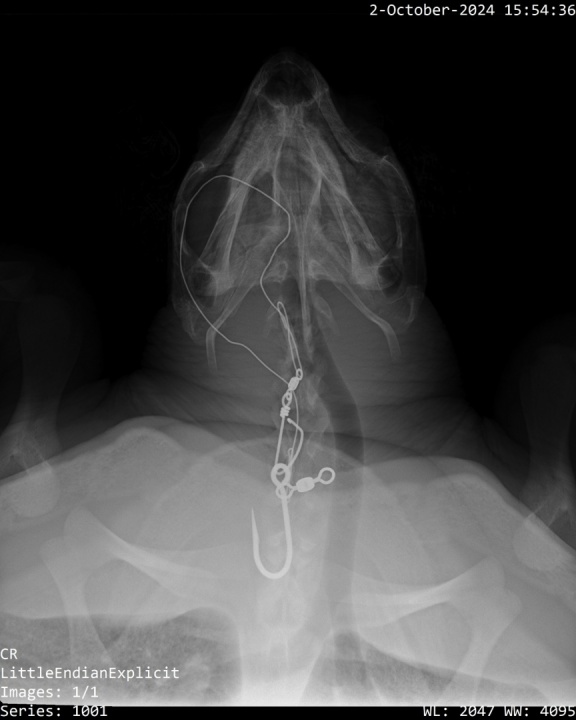

Tartaruga enredada